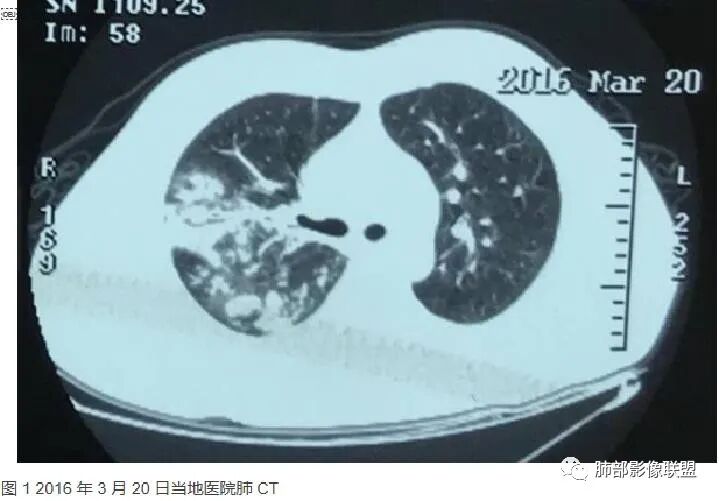

中年男性,咳嗽咳痰伴咯血胸疼,发热。双肺野多发斑片磨玻璃影实变影,结节影,结节影大小不一,主要沿支气管血管束分布,边界清楚,支气管进入,有支气管充气征,左下肺大片实变影,周围磨玻璃影,边界不清,考虑粘液腺癌并双肺转移,鉴别淋巴瘤,血管炎,机化性肺炎。

老年男性,急性起病,伴发热、咳血,双肺多发结节、片状高密度影及磨玻璃密度影,边缘模糊不清,支气管穿行,考虑感染性病变,金葡菌,建议抗炎治疗后复查除外粘液腺癌

中年男性,咳嗽发热伴咳血胸痛。以左下肺大片实变混合磨玻璃为主,另两肺散在斑片状阴影,渗出明显边缘模糊,左下肺病灶部分边缘平直,病灶内未见明显空洞气囊等,未见树芽。纵隔窗显示病灶范围明显缩小提示渗出为主,双侧胸腔未见明显积液。首诊还是感染性病变,细菌,真菌,病毒,气道播散型金葡菌?非典型肺炎?

男,52,咳嗽咳痰胸痛半月,近期加重,发热3天,声嘶伴气短1天,昨晚痰血。胸部CT:双肺多发斑片影、结节影,大小不一,密度不一,有GGO、有实性,沿支气管血管束分布,中内带多,边界不清,支气管进入,支气管充气征,似有小叶内间隔增厚,考虑:血管炎?肺水肿?鉴别感染、腺Ca、淋巴瘤等。

今天的病例复查很符合金葡菌

第一次不典型

左下肺的囊腔呈簇状分布

这个区域应该是外侧最重的,但是没有看到空洞。二元论也可以,单纯从影像看金葡也不一定都是小叶性改变的,肺泡性改变也可以,从病史看,可能病毒合并金葡。

金葡不会等到半个月还是斑片状影的,金葡变化很快,一般是按天、甚至按小时计算的。

这个炎症当时也考虑过金葡,但是病史是半个月,所以就排除了,病史不符合金葡

这个病史发热三天,胸痛可能是后面金葡引起的,这些不一定是金葡,可能就有基础疾病,合并的这个。真正的病史就是金葡引起,病史就发热三天,近期加重,这三天就是金葡的改变。

就是说这个基础病变不知道是什么,肯定有基础病变,不然不符合,因为前上个星期才去讲这个金葡的,当时一看,这个斑片斑片确实有金葡的一些特点存在,支气管壁有增厚。